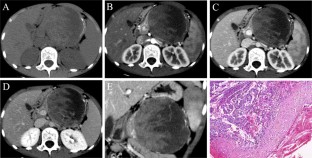

Fig. 2